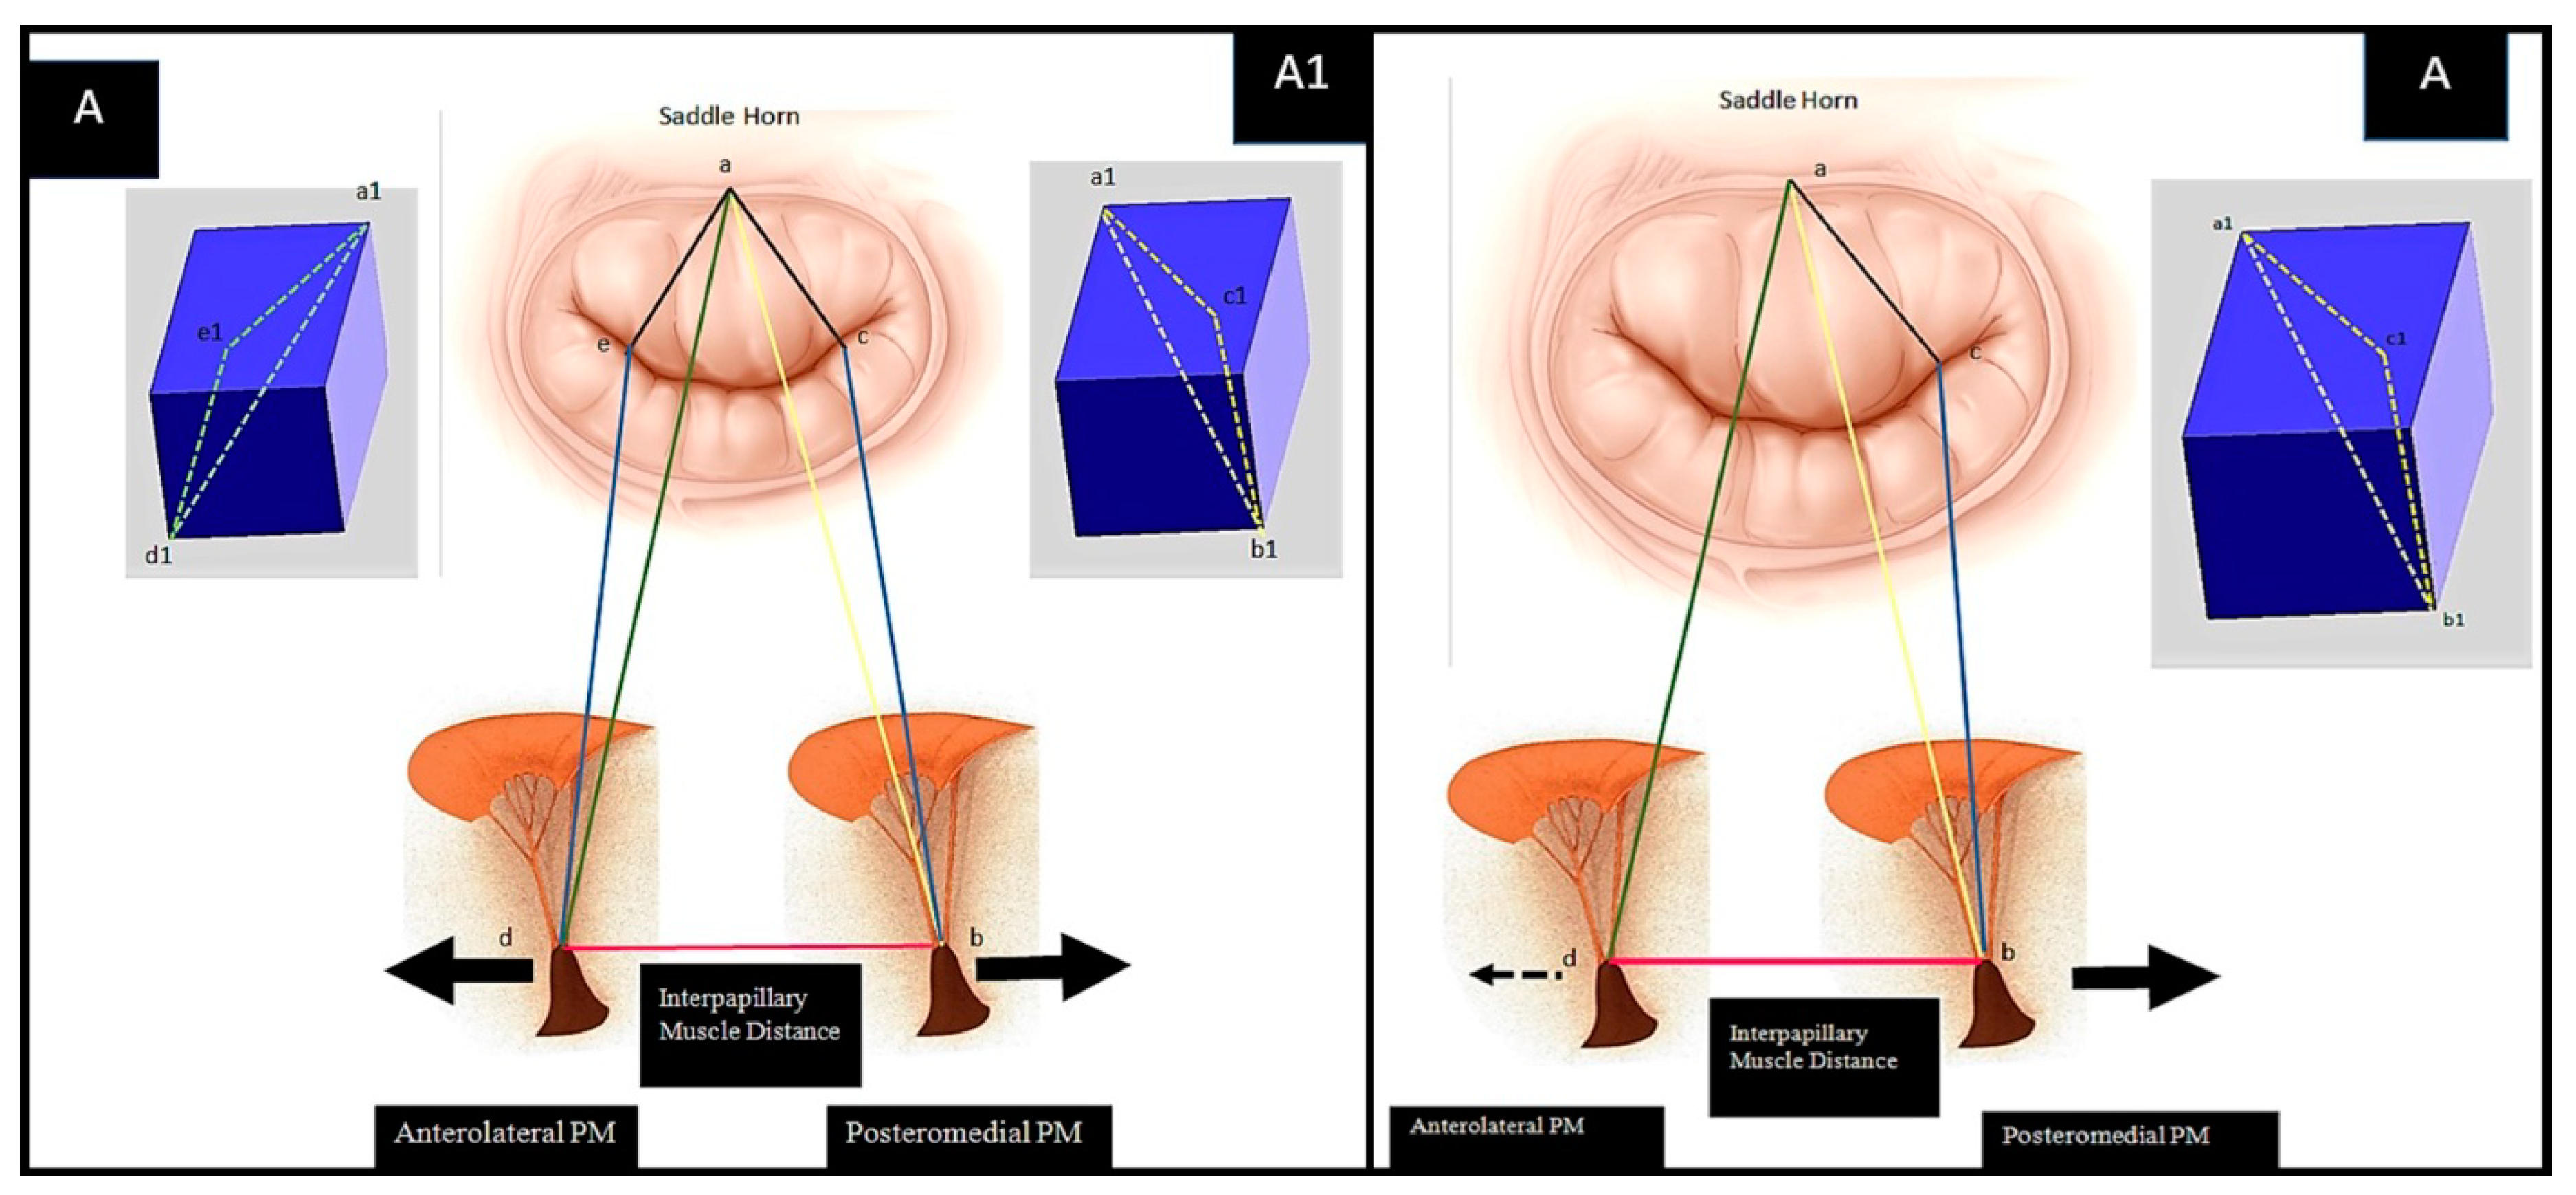

The Pre-Operative Configuration